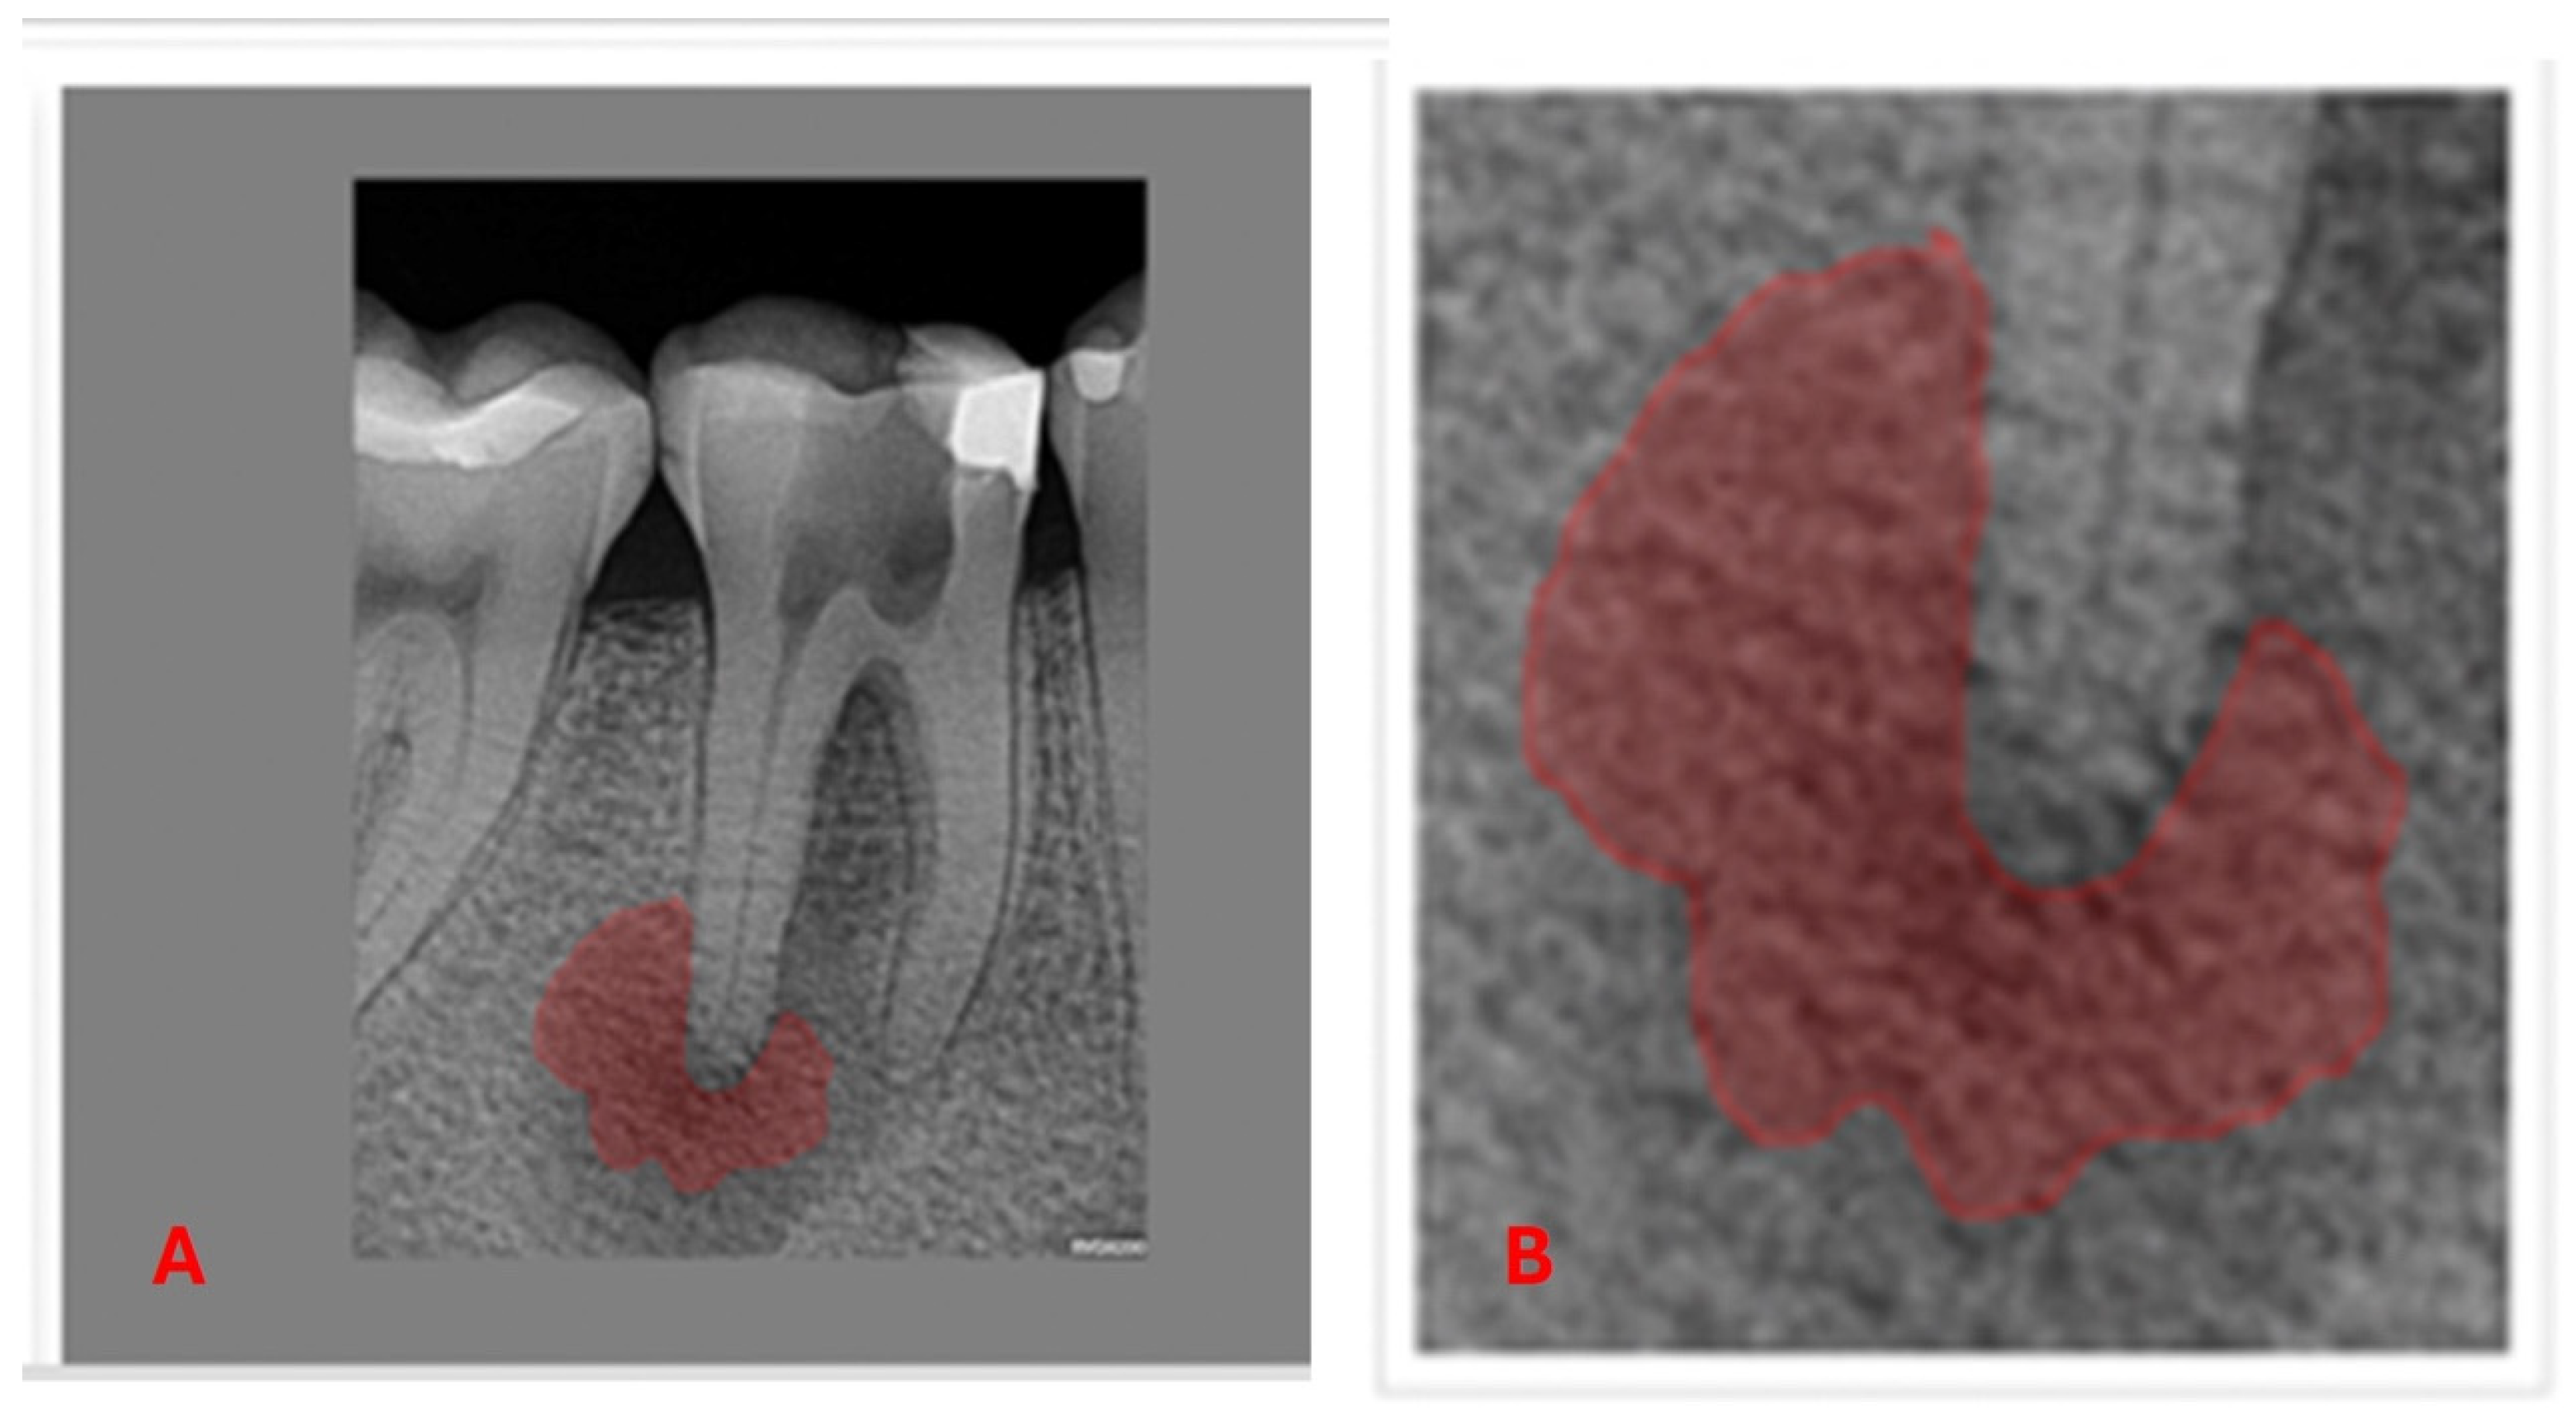

3.3. Machine Learning and Deep Learning Analysis

- Ekert, T.; Krois, J.; Meinhold, L.; Elhennawy, K.; Emara, R.; Golla, T.; Schwendicke, F. Deep Learning for the Radiographic Detection of Apical Lesions. J. Endod. 2019, 45, 917–922.e5. [Google Scholar] [CrossRef]

- Moidu, N.P.; Sharma, S.; Chawla, A.; Kumar, V.; Logani, A. Deep learning for categorization of endodontic lesion based on radiographic periapical index scoring system. Clin. Oral Investig. 2021, 26, 651–658. [Google Scholar] [CrossRef]

- Pauwels, R.; Brasil, D.M.; Yamasaki, M.C.; Jacobs, R.; Bosmans, H.; Freitas, D.Q.; Haiter-Neto, F. Artificial intelligence for detection of periapical lesions on intraoral radiographs: Comparison between convolutional neural networks and human observers. Oral Surg. Oral Med. Oral Pathol. Oral Radiol. 2021, 131, 610–616. [Google Scholar] [CrossRef]

- Sadr, S.; Mohammad-Rahimi, H.; Motamedian, S.R.; Zahedrozegar, S.; Motie, P.; Vinayahalingam, S.; Dianat, O.; Nosrat, A. Deep Learning for Detection of Periapical Radiolucent Lesions: A Systematic Review and Meta-analysis of Diagnostic Test Accuracy. J. Endod. 2023, 49, 248–261.e3. Available online: https://linkinghub.elsevier.com/retrieve/pii/S0099239922008457 (accessed on 17 January 2023). [CrossRef]